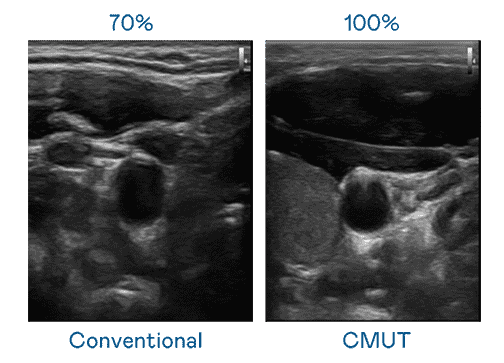

CMUT 技术是一种用电容式微机电元件来产生超音波讯号的技术。。与传统 PZT 压电式技术相比,,,CMUT 频宽增加 30%,,,,更宽频的超音波讯号让影像解析度大幅提升,,是实现高影像品质医疗超音波扫描、、、、促进精准医疗发展的关键技术。。。

大频宽带来超清晰影像

超音波影像的解析度高低,,首先取决于探头能发出的讯号频宽。。JDB电子 CMUT 可提供高清晰的超音波讯号,,提供高频宽、、、高灵敏度、、、影像纹理细节更高的超音波影像,,协助医护人员缩短影像判读时间及利用精准的医疗影像进行诊断。。